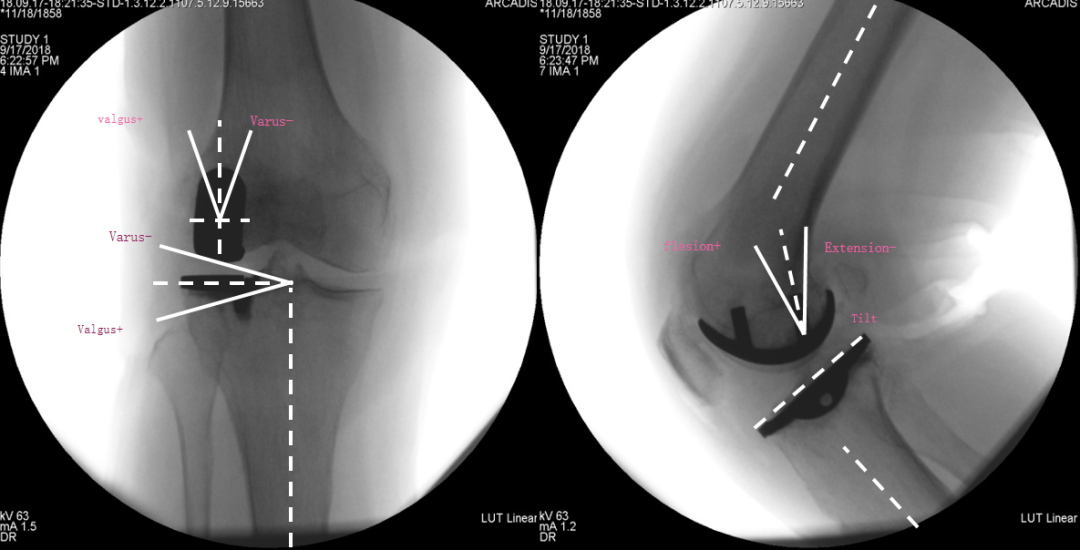

假体位置分析

正位片标准胫骨和股骨假体位置

AP位假体位置:胫骨假体轻度外翻,外侧缘与胫骨平台外侧缘齐平; 股骨假体长轴与胫骨假体垂直,与胫骨假体中线一致。

侧位片标准胫骨和股骨假体位置

侧位片假体位置:股骨假体后倾38°,假体后缘与股骨后髁齐平,胫骨假体后倾3°,与胫骨平台前后缘齐平。

股骨假体偏内放置

AP位胫骨与股骨假体位置:股骨假体中轴线与胫骨假体中线不一致,偏内侧,且外翻。

股骨假体偏外放置

AP位胫骨与股骨假体位置:股骨假体中轴线与胫骨假体中线不一致,偏外侧,且内翻

矫正不足、矫枉过正